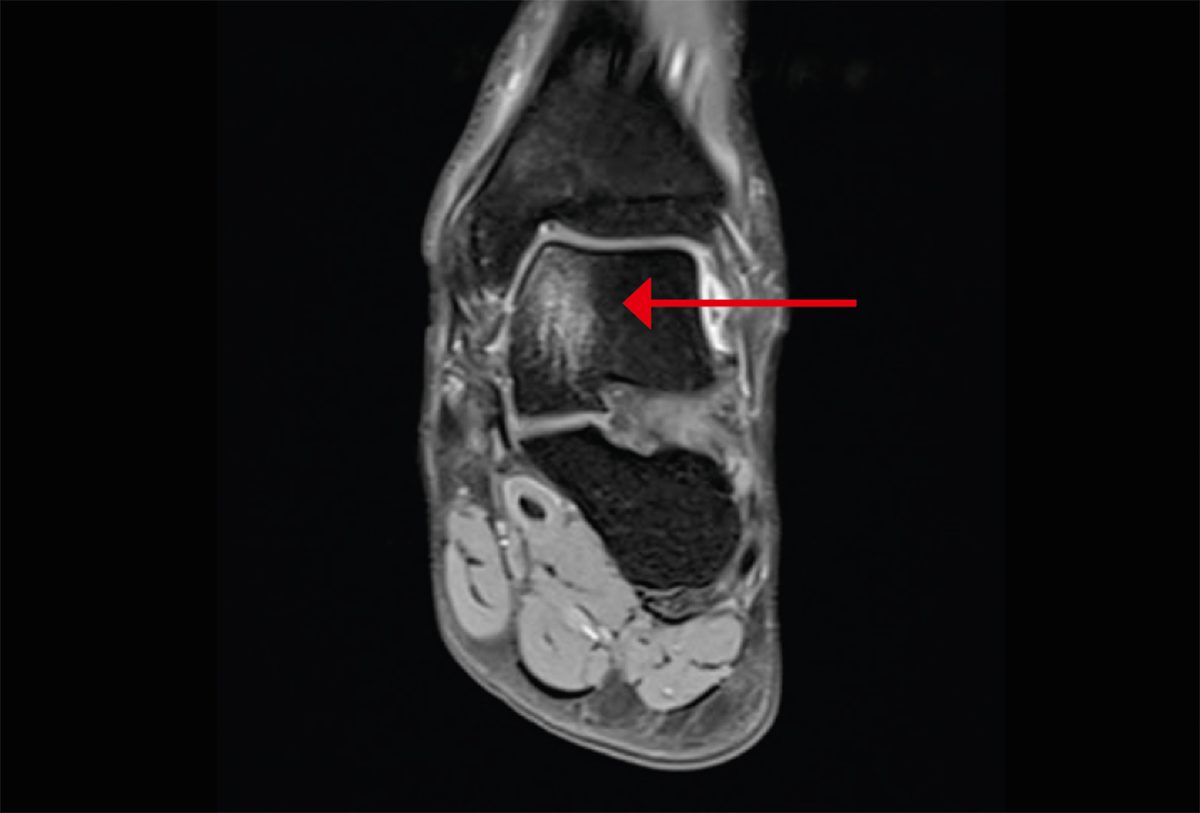

From www.researchgate.net

Typical appearance of talar bone marrow edema observed on MR images of... Download Scientific Talus Bone Marrow Edema bone marrow edema is when fluid builds up in your bone marrow. bone marrow edema syndrome of the foot and ankle, also known as transient bone marrow edema syndrome of the foot. Your doctor may call it bone marrow lesions. bone marrow edema is a potentially serious condition where fluid builds up inside your bone marrow (the. Talus Bone Marrow Edema.